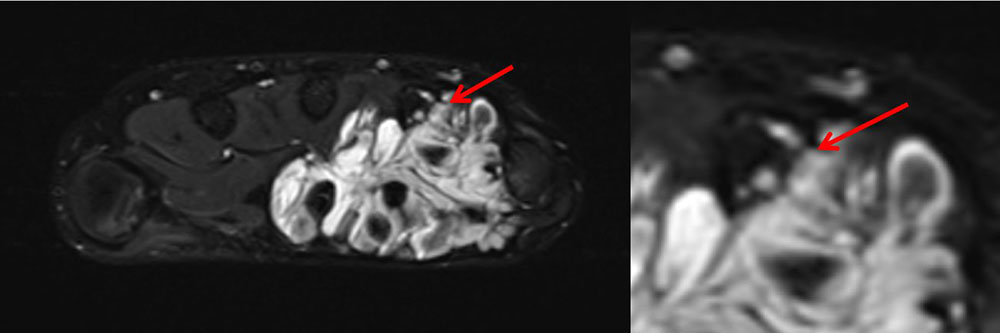

These clearly elevated D-dimer levels in patients with venous malformations, who may be otherwise quite healthy, do not occur in any other disease and are thus an important differential diagnostic component. Stagnant blood within the venous malformation results in classic fluid-fluid levels on imaging due to corpuscular blood components sinking with gravity in the absence of blood flow.

Clinically, there is local pain, local induration and swelling. If thrombophlebitis is superficial on the skin, local redness is often visible as well. The duration of this circumscribed inflammation within the venous malformation ranges from a few hours to 3 to 5 days, sometimes longer. D-dimer levels are further elevated during such thrombophlebitis.

The normal organizing degradation of larger local thrombi or thrombophlebitis can lead to collagen deposition, which is palpable as a circumscribed induration over a longer period of time. If the thrombus then still cannot be completely degraded in the venous malformation, calcium deposition and increasing local, shell-like or popcorn-like calcification will occur over time. The final form is the calcified phlebolith as a round calcified lesion 1 cm in size on X-ray images of the venous malformation.